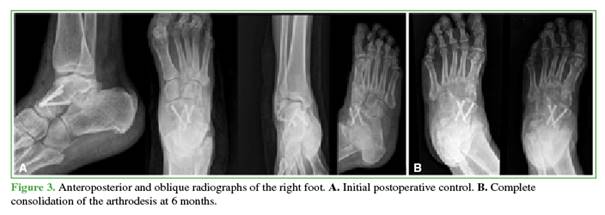

A dorsal approach was performed in the midfoot over the area of deformity. Using blunt dissection, the extensor hallucis longus tendon and the dorsalis pedis artery were retracted laterally, and the anterior tibial tendon medially. The joint capsule was incised, and the fibrous tissue interposed in the talonavicular space was removed. The remaining cartilage from both bones was debrided using a blade, distractor, and a reaming drill. Headless compression screws were placed, and a bone substitute was applied to the arthrodesis site as well as to the articular defect of the talus. In this case, no procedures were performed for the cuboid fracture, which was chronic, with a sagittal fracture line and minimal displacement.

Postoperatively, control radiographs were obtained, analgesia was administered, and intravenous antibiotic prophylaxis was given for 24 hours. Early rehabilitation was indicated by the physiatry team.

The patient was discharged. At the 3-week follow-up visit, sutures were removed. Weight-bearing was restricted for 8 weeks, after which progressive loading was allowed.

At the conclusion of follow-up, 18 months postoperatively, the patient had a stable, plantigrade, pain-free foot.

The American Orthopaedic Foot and Ankle Society (AOFAS) score was 87.